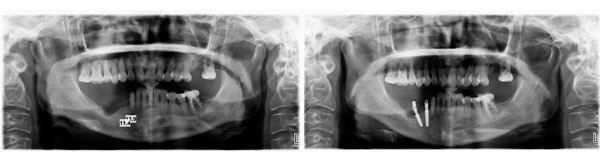

患者右下四、五种植修复